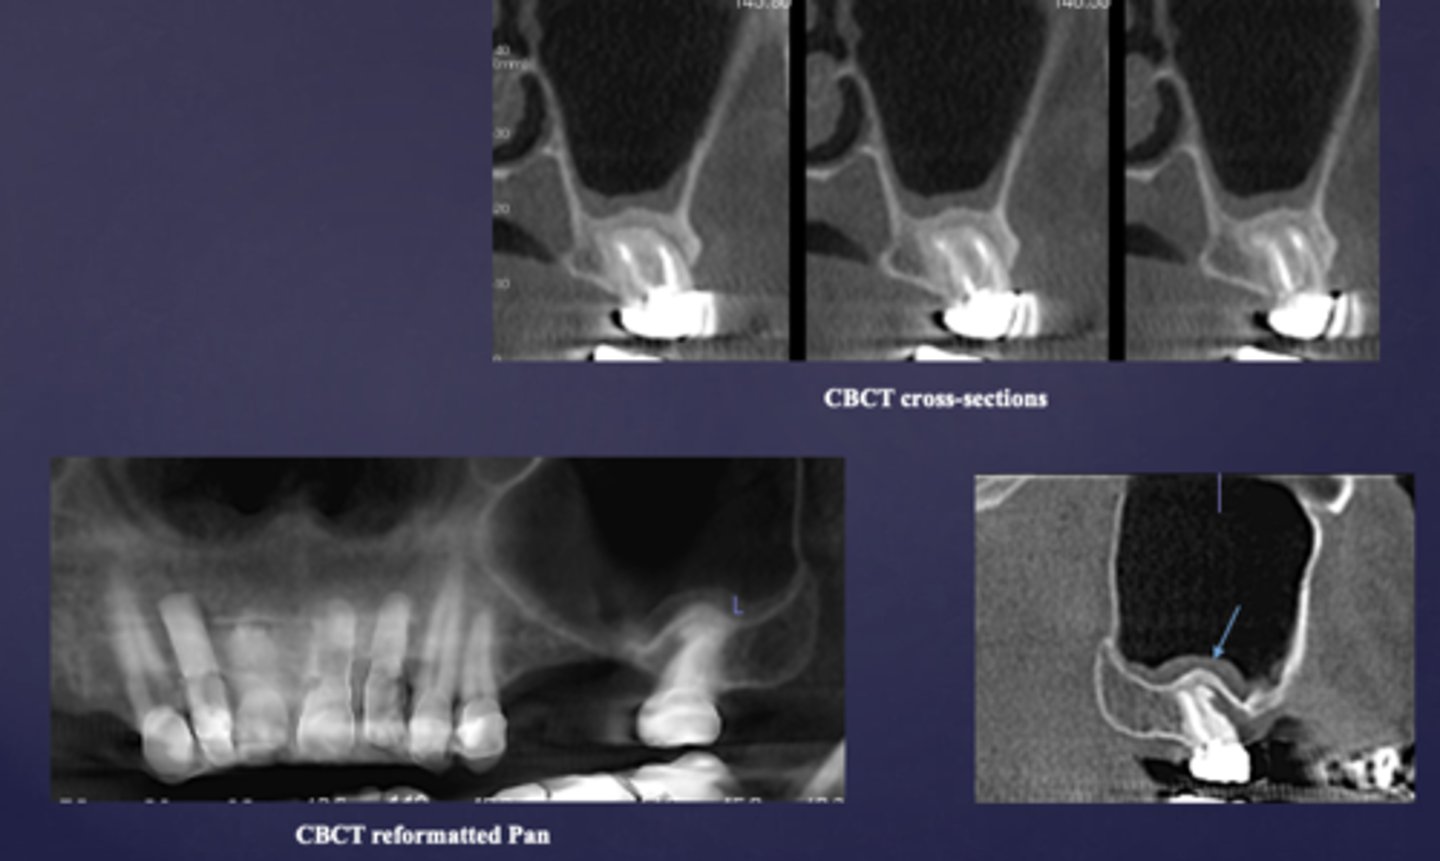

What is the imaging method of choice for osteomyelitis

CBCT

What is happening here?

periosteal reaction

Proliferative periostitis is also known as what?

onion skin